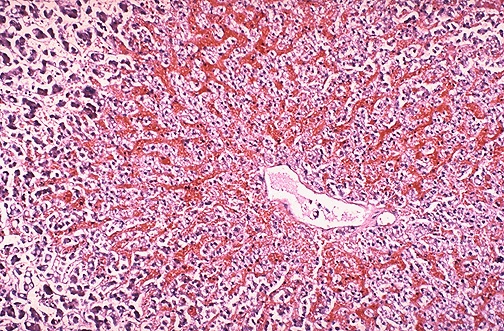

Microscopically, the nutmeg pattern results from congestion around the central veins, as seen here. This is usually due to a "right sided" heart failure.